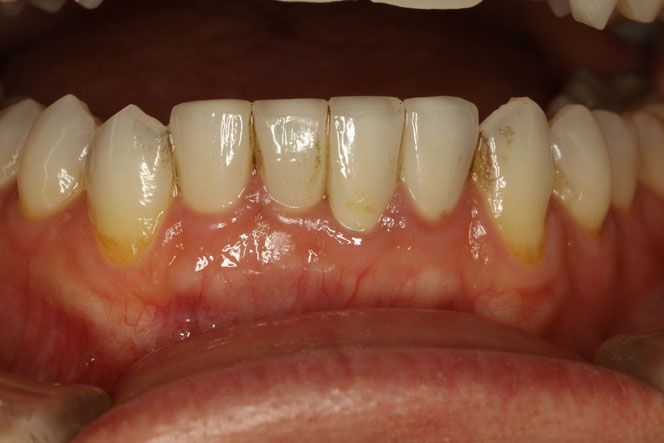

写真では、オールセラミックが天然の歯のような透明感があります。また歯茎が黒ずまないのも特徴です。

治療前、差し歯の色の変色及び、歯茎の腫れが見られます。

差し歯に汚れがついてしまっています。

オールセラミックにて治療後の状態。歯茎の状態が改善して引き締まっています。

オールセラミックは汚れがつきにくいため、歯茎の炎症が起こりにくくなります。